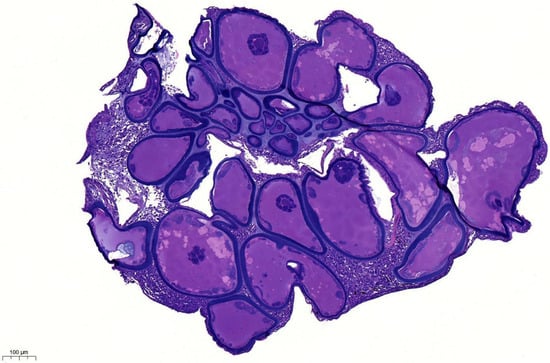

3.1. Histopathology